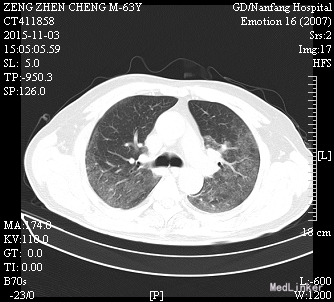

患者诉仍有咳嗽咳痰、呼吸困难、胸闷气促,咳白色粘痰,平卧及活动时加重,坐起后缓解,无发热,无咯血,精神、睡眠一般,饮食欠佳,大小便正常。高流量吸氧(7L/min)下血氧饱和度维持在93-95%,心率65-75次/分。查体:神志清楚,查体合作,胸廓未见异常;双肺呼吸音粗,双侧肺可闻及少许细湿罗音,无胸膜摩擦音;心界不大,心律齐,各瓣膜听诊区未闻及病理性杂音;腹平坦,无压痛、反跳痛,肝脏肋下未触及。辅助检查:感染三项:降钙素原(ProCT)6.00ng/ml;淀粉样蛋白A(SAA)281.8mg/L;C反应蛋白(CRP)。真菌D-葡聚糖(1_2_3βD)315pg/mL。巨细胞病毒定量(FQ_HCMV)2.85E+3copies/m。凝血功能:血浆D-二聚体测定(D-Dimer)0.85mg/L FEU;活化部分凝血活酶时间(APTT)46.8秒;血浆凝血酶原时间测定(PT)14.0秒。肾功能:尿素(BUN)19.52mmol/L;肌酐(CR)223μmol/L。肝功能:丙氨酸氨基转移酶(ALT)79U/L;天门冬氨酸氨基转移酶(AST)60U/L;总蛋白(TP)54.3g/L;白蛋白(ALB)21.8g/L150.67mg/L。前-脑利尿肽(Pro-BNP)572.1pg/mL。胸片示:1、两肺炎症,较前进展,建议治疗后复查;2、主动脉硬化;3、左肾区致密影,请结合临床其他检查;4、右第4肋骨陈旧骨折。

肾移植术后肺 部感染多发生在术后的早期,多数是在术后2~4月期间感染的。与这期间免疫抑制剂用量大,机体抵抗力低下有关。新型免疫抑制剂的临床应用,提高了肾移植的成功率,但也导致了机体免疫力降低,增加了各种感染的机会,以肺部感染最为常见,已成为肾移植患者死亡的主要原因。早期诊断和治疗对其预后尤为重要。 肾移植术后肺部感染早期的临床表现往往不典型,发热是其最常见、最主要的早期症状有发热,占 90%;许多患者入院时只有发热,开始为低热,咳嗽、咯痰、双 肺罗音均不明显,随后3-5天体温可达38.5℃以上;X线胸片已经显示肺部有点、片状阴影;病情发展迅速,咳嗽、咯痰及肺部罗音出现,患者很快会出现胸闷、呼吸困难、血氧饱和度下降,血气分析可有不同程度的低氧血症。所以肾移植术后早期出现发热,一定要摄胸片(或反复摄胸片),查白细胞计数,必要时行纤维支气管镜检查,或按肺部感染处理(排除排异反应)。 病原体的检测至关重要,需要反复、多次查血和痰的细菌、霉菌培养、痰涂片,必要时可行纤维支气管镜取分泌物查找病原菌。肾移植术后病毒感染较常见,特别是巨细胞病毒(CMV)最常见;由于CMV在正常人群中广泛存在,但多无临床症状,在免疫力低下时可使潜在的病毒复活、复制,导致肺部感染,死亡率高。激素对潜在的CMV复活影响很小,免疫抑制剂(如CSA、FK506等)可加速CMV的复制;CMV肺部感染无特异性,表现为高热、干咳、呼吸急促、白细胞减少,胸片多以片状或散在点片状影为主,也可扩散至全肺,呈间质性肺炎的表现;虽然获得CMV感染的直接证据很难,但PCR-CMV -DNA和CMV-IgM的检测可作为诊断依据。更昔洛韦对CMV感染治疗效果较好。 肾移植患者由于长期大量的用免疫抑制剂、肾上腺皮质激素,使机体抵抗力下降,加之强效广谱抗生素的应用,易造成机体菌群失调,导致二重感染,使机体正常分布的真菌大量繁殖、扩散。可适当抢先治疗,本例用卡泊芬净取得较好效果。肾移植术后肺部感染患者病情进展迅速,伴随着高热,可出现胸闷、呼吸困难、血氧饱和度下降等;治疗上除抗感染、化痰止咳外,必要 用呼吸机辅助呼吸,改善肺通气功能,提高血氧分压;可先采用无创的面罩吸氧,如氧合不满意,则改用有创的气管插管辅助通气,本例患者用无创呼吸机辅助通气取得较好效果。